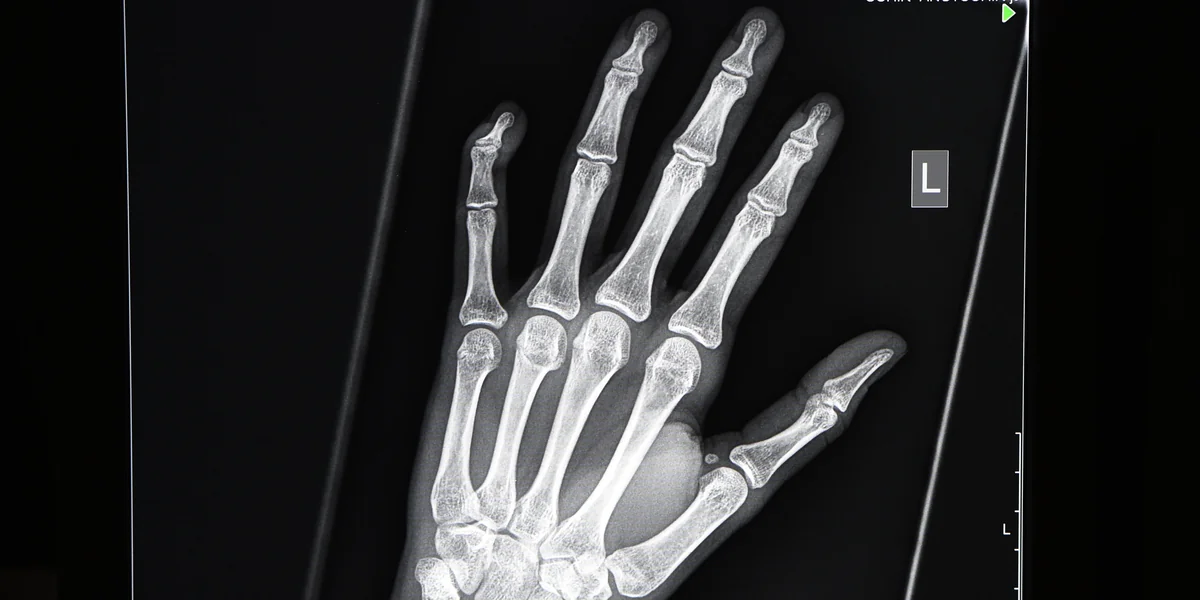

Finger weg! Künftig machen sich korrupte Ärzte strafbar. Foto: dpa